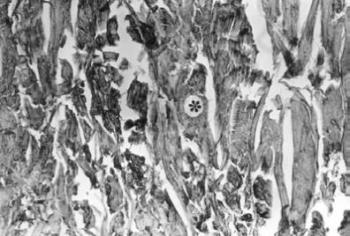

23. ábra. A prostata simaizom sejtjeiben kifejezett desmin-pozitivitás látható. 19. századi múmia. Desmin-ABP reakció, 100× nagyítás

24. ábra. Sztereomikroszkópos felvétel a sípcsont bokanyúlványának csontszerkezetéről. 20× nagyítás